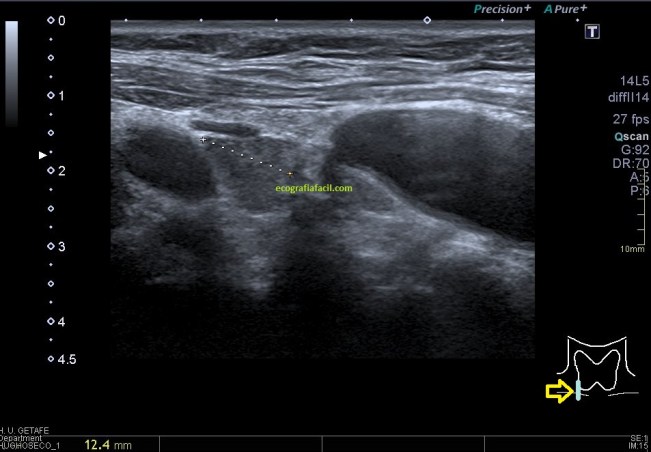

Una vez que hemos encontrado la lesión, es momento de estudiarla detenidamente, su aspecto, tamaño bordes y vascularización son vitales para que la radióloga pueda efectuar un informe.

La imagen 3 y 4 son parte estudian en eje largo y corto las medidas de la lesión en los tres ejes del espacio, en ocasiones, podemos tener más de una lesión. Siempre super atentos si las lesiones son intra o extratesticulares.